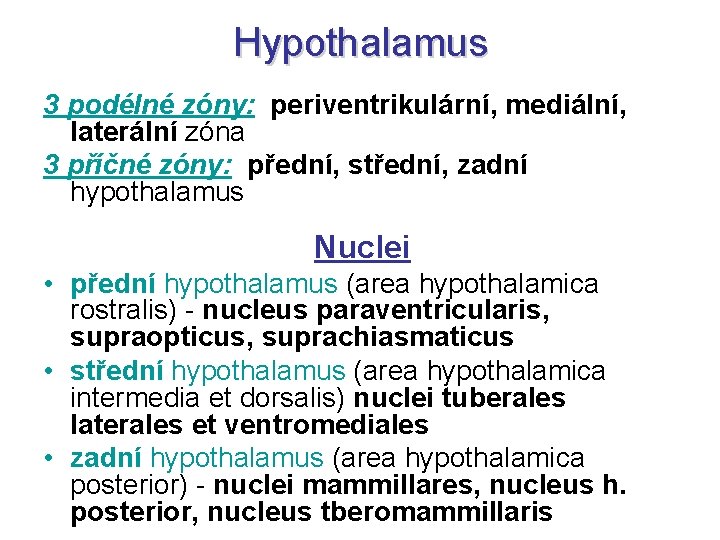

Hypothalamus 3 podélné zóny: periventrikulární, mediální, laterální zóna 3 příčné zóny: přední, střední, zadní hypothalamus Nuclei • přední hypothalamus (area hypothalamica rostralis) - nucleus paraventricularis, supraopticus, suprachiasmaticus • střední hypothalamus (area hypothalamica intermedia et dorsalis) nuclei tuberales laterales et ventromediales • zadní hypothalamus (area hypothalamica posterior) - nuclei mammillares, nucleus h. posterior, nucleus tberomammillaris